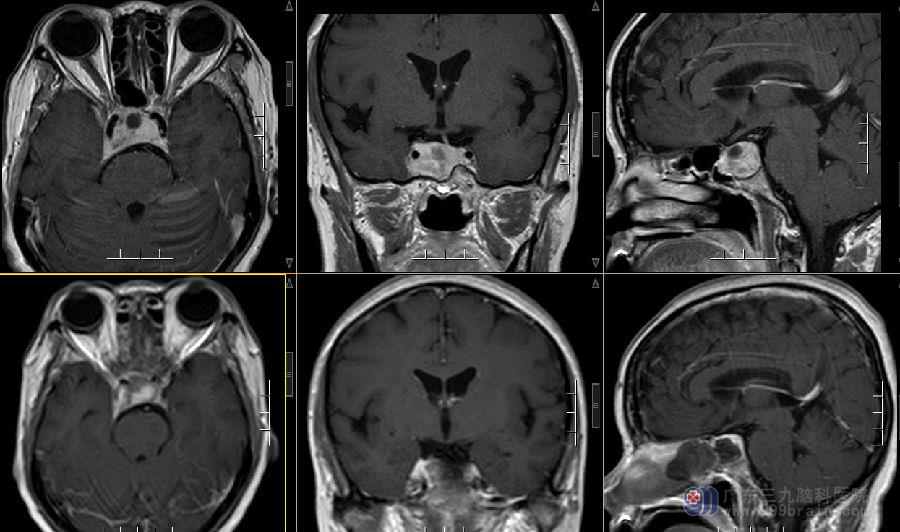

图2:术前MR示鞍区示一团块状囊实性占位性病变,实性部分呈等T1等T2信号,增强扫描明显强化,大小约27×23×19mm,病变包绕双侧颈内动脉,以右侧为著,右侧海绵窦受侵犯。垂体柄左偏,视交叉略受压。鞍底及鞍背骨质吸收变薄。

图3:术前术后MR示经鼻道-蝶窦呈术后改变,原鞍区病灶呈切除术后。